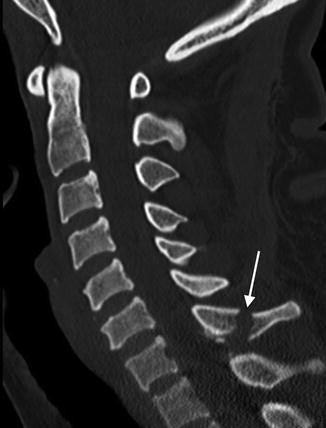

Sagittal CT of the cervical spine displays a mild distracted fracture of the C7 spinous process (arrow) without malalignment in a 35-year-old patient following a motor vehicle accident. Of note, the intracanalicular contents include the spinal cord that cannot be reliably assessed on this image